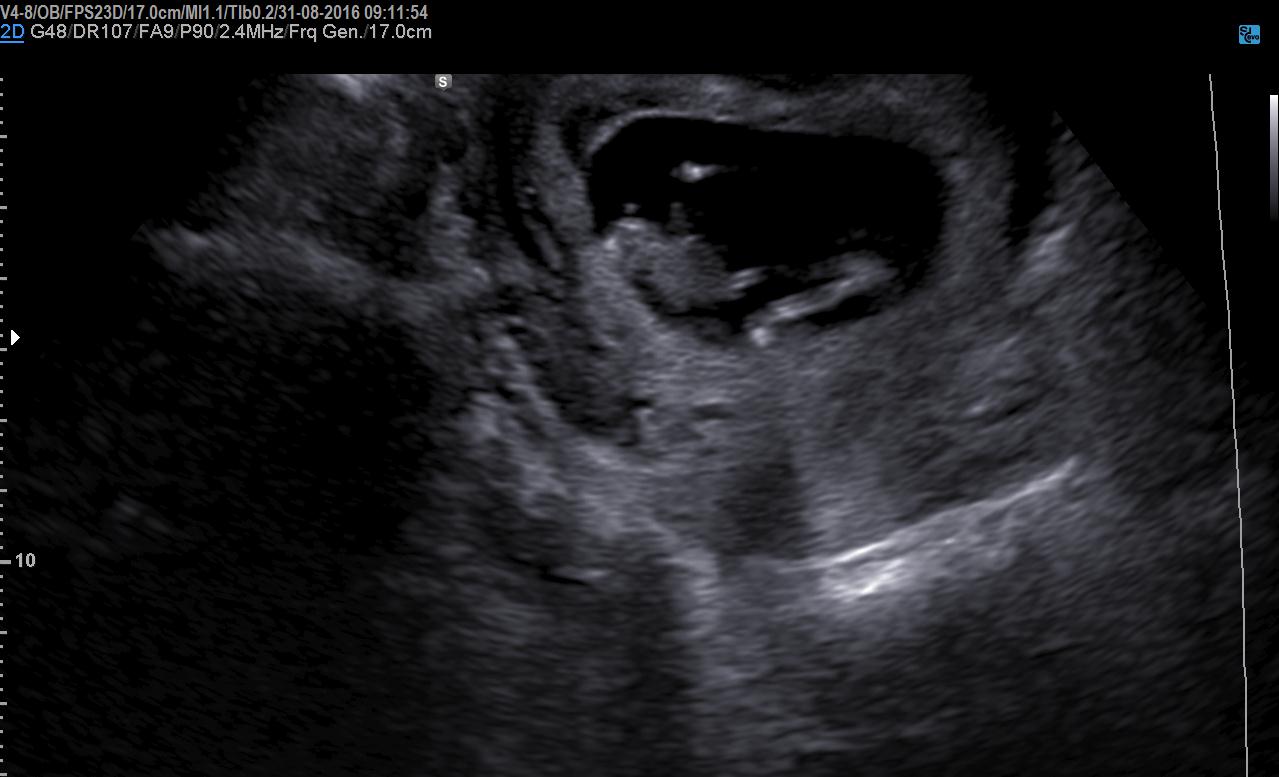

Girl or boy nub??? HELP pls any guesses

Hi guys. Boy or girl nub??

Attachment 33220